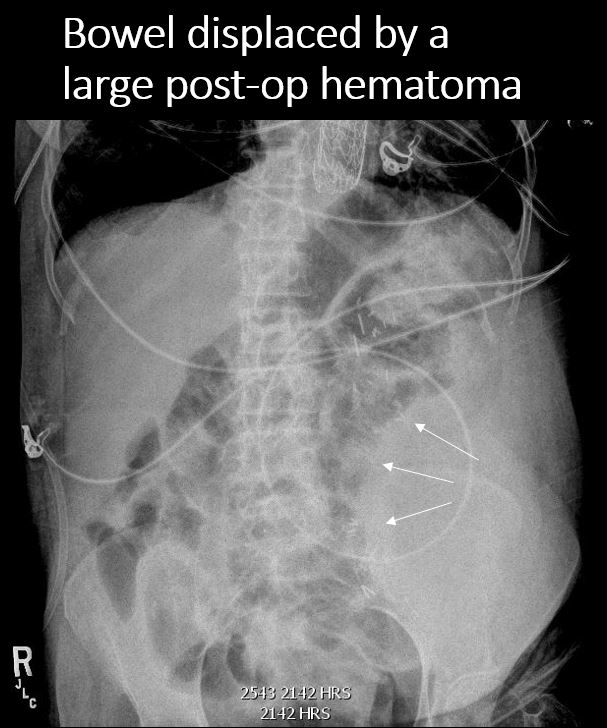

There is a soft tissue mass.

There is an extrinsic mass effect.